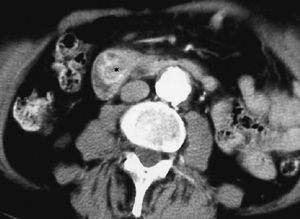

El linfoma intestinal también asienta con mayor frecuencia en el íleon. Aparece como un engrosamiento de pared, a veces nodular, que puede ser focal o difuso, que característicamente no produce estenosis de la luz intestinal, pudiendo producir una dilatación aneurismática del segmento afectado. La presencia de adenopatías viscerales o retroperitoneales, así como esplenomegalia puede sugerir el diagnóstico (fig. 20)22,24. Los tumores estromales malignos pueden alcanzar un tamaño considerable, apareciendo en la TC como masas heterogéneas con zonas internas hipodensas, debido a su tendencia a la necrosis y hemorragia, con realce periférico de contraste. Los malignos pueden invadir órganos vecinos, diseminarse al peritoneo o dar metástasis hepáticas, pero no suelen asociar adenopatías21,25,26.

Fig. 20--Linfoma duodenal. (A) Ecografía. (B) Tomografía computarizada con contraste intravenoso que muestra un engrosamiento circunferencial de la pared duodenal (D) con adenopatías mesentéricas y retroperitoneales (flechas).